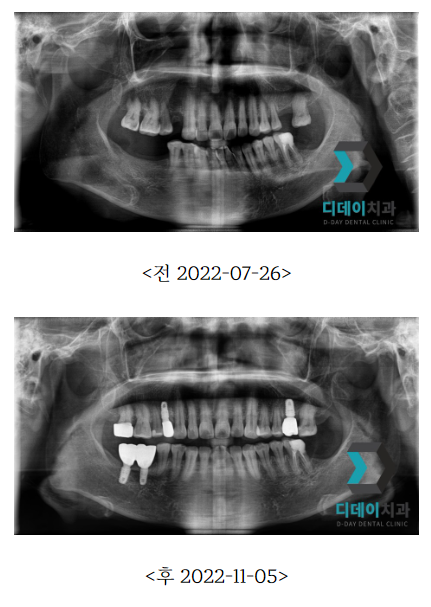

| 본 게시물은 의료광고법 제56조 1항을 준수하여, 의료 정보 제공 및 병원 홍보를 목적으로 디데이치과의원에서 직접 작성하였습니다.다만, 블로그에서 제공해 드리는 정보는 참조용으로만 활용하시고, 정확한 개인의 증상 파악은 의료기관에 직접 내방하시어 의료진을 통해 확인하실 것을 권유 드립니다.치과에서 진행되는 모든 시술 및 수술(임플란트 포함)은 개인에 따라 부작용 (염증, 출혈, 부기, 감염, 신경 손상, 마비 등) 가능성이 있습니다. 따라서 사전에 의료진과 충분한 상담을 통해 결정하시길 바랍니다.게시물의 치료 사진은 실제 본원에서 모든 치료 과정을 마친 환자분의 동의하에 촬영되었습니다. 전후 사진은 동일인이며, 동일 조건하에 촬영되었음을 밝힙니다. |